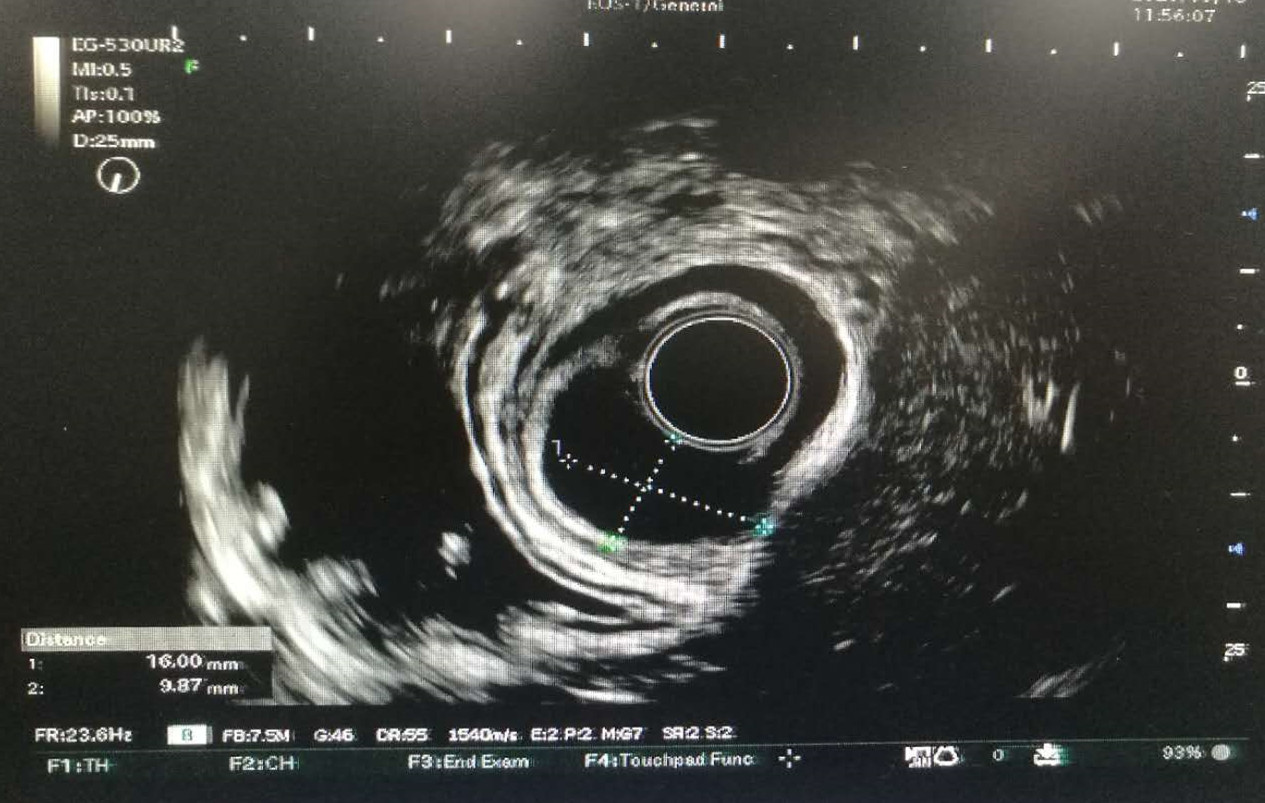

梁女士在外院行胃镜检查发现自己胃底有肿物,这让她忧心忡忡。后来她和家人打听到我院可通过内镜技术治疗后,便慕名来到消化内科住院就诊,其科室姚朝光主任了解病人及家属的顾虑后,立即组织医护团队结合患者的检查结果讨论制定治疗及术后护理方案,将择期进行手术。在讨论的过程中,发现梁女士的超声胃镜检查提示胃底肿物(平滑肌瘤?间质瘤?大小约2.8cmx2.5cm),该病变起源于固有肌层的位置深,常规内镜下治疗常难以完整切除病变。在以往多需要外科手术或腹腔镜切除,但因外科治疗的创伤较大,对消化道正常功能的影响也比较大,且住院时间长、医疗费用高、恢复慢,经与患者及家属沟通后一致选择通过内镜治疗。